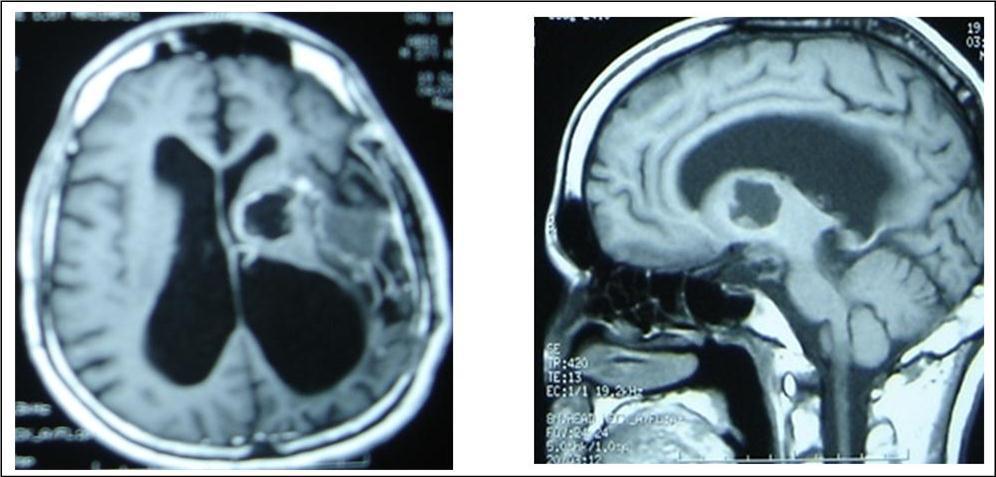

A 27 years-old male patient was admitted with 1 month history of headache, fever, short term memory lack, aphasia, right hemiparesis and seizures. He had liver hydatid cysts excised 8 years before and was treated with adjuvant medication (albendazole). The neurological examination revealed right central third cranial nerve palsy and hemi paresis, with Babinski sign positive, aphasia and papilledema on ocular fundus. The Glasgow Coma Scale was evaluated to 10/15 (E:3; V:1; M:6). A brain CT scan showed a large left temporoparietal intracerebral multiple and calcified hydatid cysts, important mass effect with midline shift about 7 mm following by an obstructive hydrocephalus (Figure 1). Other cysts were found in thalamic region (Figure 2). The Thoraco-abdominal CT scan showed multiple intra peritoneal hydatid cysts (Figure 3). A left temporo parietal craniotomy was performed in emergency. After corticectomy, using Arana-Iniguez technique, the appearance of the capsule suggested infected hydatid cysts with a purulent material which was aspirated. Numerous hydatid cysts were lifted away and several daughter vesicles were carefully removed without rupture (Figure 4). Macroscopically, the abscess wall appeared to be thick, calcified and tightly attached to lateral ventricular, so it could not be removed. The deep cyst overlying the third ventricle was left.in place. Microscopic examination demonstrated live scoleces, protoscoleces and multiple hooks. These findings are consistent with hydatid cyst (granulosis ecchinococcus) (Figure 5). Bacteriology examination found several white blood cells in the pus (neutrophilia) and infection by streptococcus pneumonia. This was consistent with infection. After surgery, the patient had medication (albendazole, specific antibiotherapy and phenobarbital). The inflammation assessment in the blood showed leukocytosis, a high C-reactive protein rate and increased erythrocyte sedimentation rate. Post operative CT scan was performed and showed the residual calcified capsule and decreased ventricular size (Figure 6). Clinical improvement was achieved after treatment. One month after the initial diagnosis, CT scan of the brain showed no recurrence and a physical examination revealed a neurologically intact, fully functional patient and eyes fundus normal. He was discharged and went to abdominal surgery two months later with complete intra abdominal cysts removal. Albendazole treatment was continuing for six months and radiological exploration was performed by brain MRI with spectroscopy at three and six month later. This showed that infection had resolved and the deep cyst overlying the third ventricle is less spherical (Figure 7, Figure 8). Four years later, the outcome was good.

Figure 1.axial CT scans of brain showing multiple hydatid cysts (A) with calcified capsule (B).

Figure 7.sagittal and axial T1 C+ MRI showing the residual capsule and deep cyst.

Figure 8.sagittal T1 C+ MRI and axial spectroscopy showing the residual capsule and deep cyst which is less spherical.